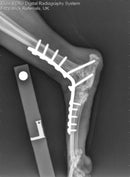

Obwohl das Anbringen einer Platte im cranialen Anteil mehr Präparation des Weichteilgewebes bedarf, hat es den Vorteil, dass diese sehr effektiv ist. In der Vergangenheit waren die Arthrodeseplatten im Winkel von 120˚ gebogen, aber VI hat jetzt, in Zusammenarbeit mit Noel Fitzpatrick, eine craniale Arthrodeseplatte entworfen, die die Löcher in den richtigen Positionen hat und durch deren Winkelung der Talus fixiert werden kann. Diese Hybridplatte hat im distalen Abschnitt kleinere Löcher. Jetzt in der neuen Größe für 2,4 mm Schrauben erhältlich. Craniale Pantarsalplatte für Hunde Obwohl mehr Weichteilgewebe präpariert werden muss, hat der craniale Zugang den Vorteil, dass die Metatarsalknochen nicht miteinander verschraubt werden. Die Stabilität im Talocruralgelenk wird mittels einer Schraube erzielt, die durch die Platte und quer durch das Gelenk in den Calcaneus geschraubt wird.